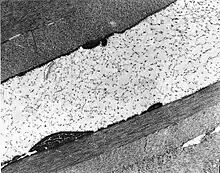

The cornea is particularly opaque in the anterior stroma by slit-lamp biomicroscopy. |

Congenital stromal corneal dystrophy (CSCD) is an extremely rare, autosomal dominant form of corneal dystrophy.[1] Only 4 families have been reported to have the disease by 2009.[2] The main features of the disease are numerous opaque flaky or feathery areas of clouding in the stroma that multiply with age and eventually preclude visibility of the endothelium. Strabismus or primary open angle glaucoma was noted in some of the patients. Thickness of the cornea stays the same, Descemet's membrane and endothelium are relatively unaffected, but the fibrils of collagen that constitute stromal lamellae are reduced in diameter and lamellae themselves are packed significantly more tightly.